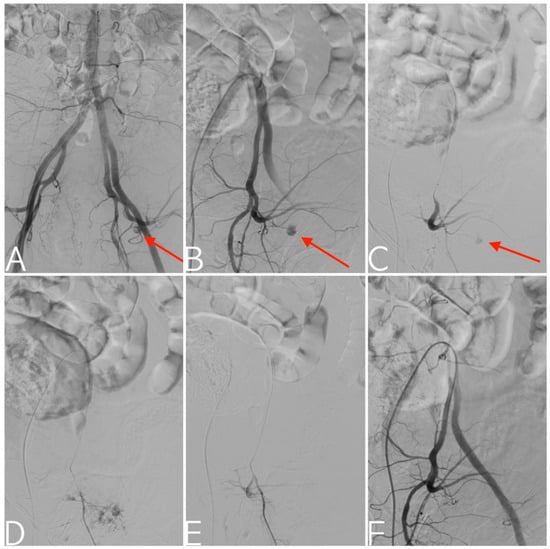

2.2. Treatment